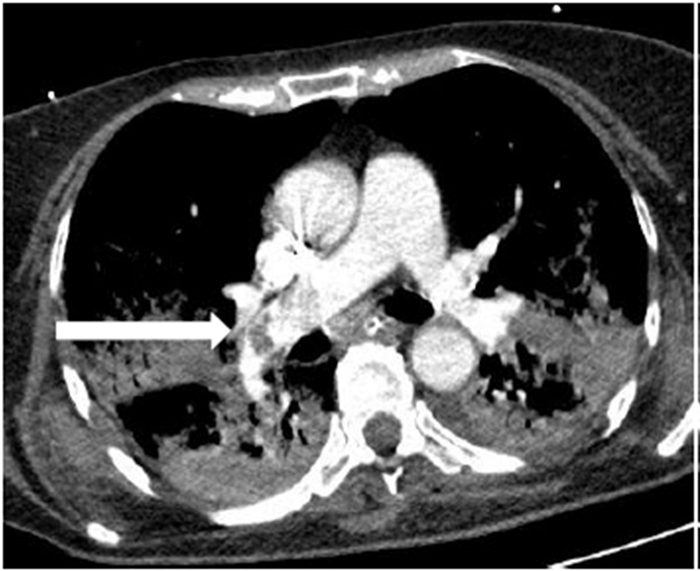

Todos los pacientes de la serie tenían hipoxia y aumento de las cifras de Dímero D con normalización en la cifra de otros parámetros típicamente alterados en esta enfermedad. De los ocho pacientes con TEP solo en dos había afectación múltiple y en ramas principales y lobares (Figura 1). En uno de los dos casos días después se confirmó la existencia de una extensa trombosis de las venas iliacas y femoral derecha como causa del TEP (Figura 2). En los otros seis casos el trombo era único y en ramas de pequeño calibre (Figura 3). En uno de los pacientes el trombo afectaba a la vena pulmonar superior izqda (Figura 4).